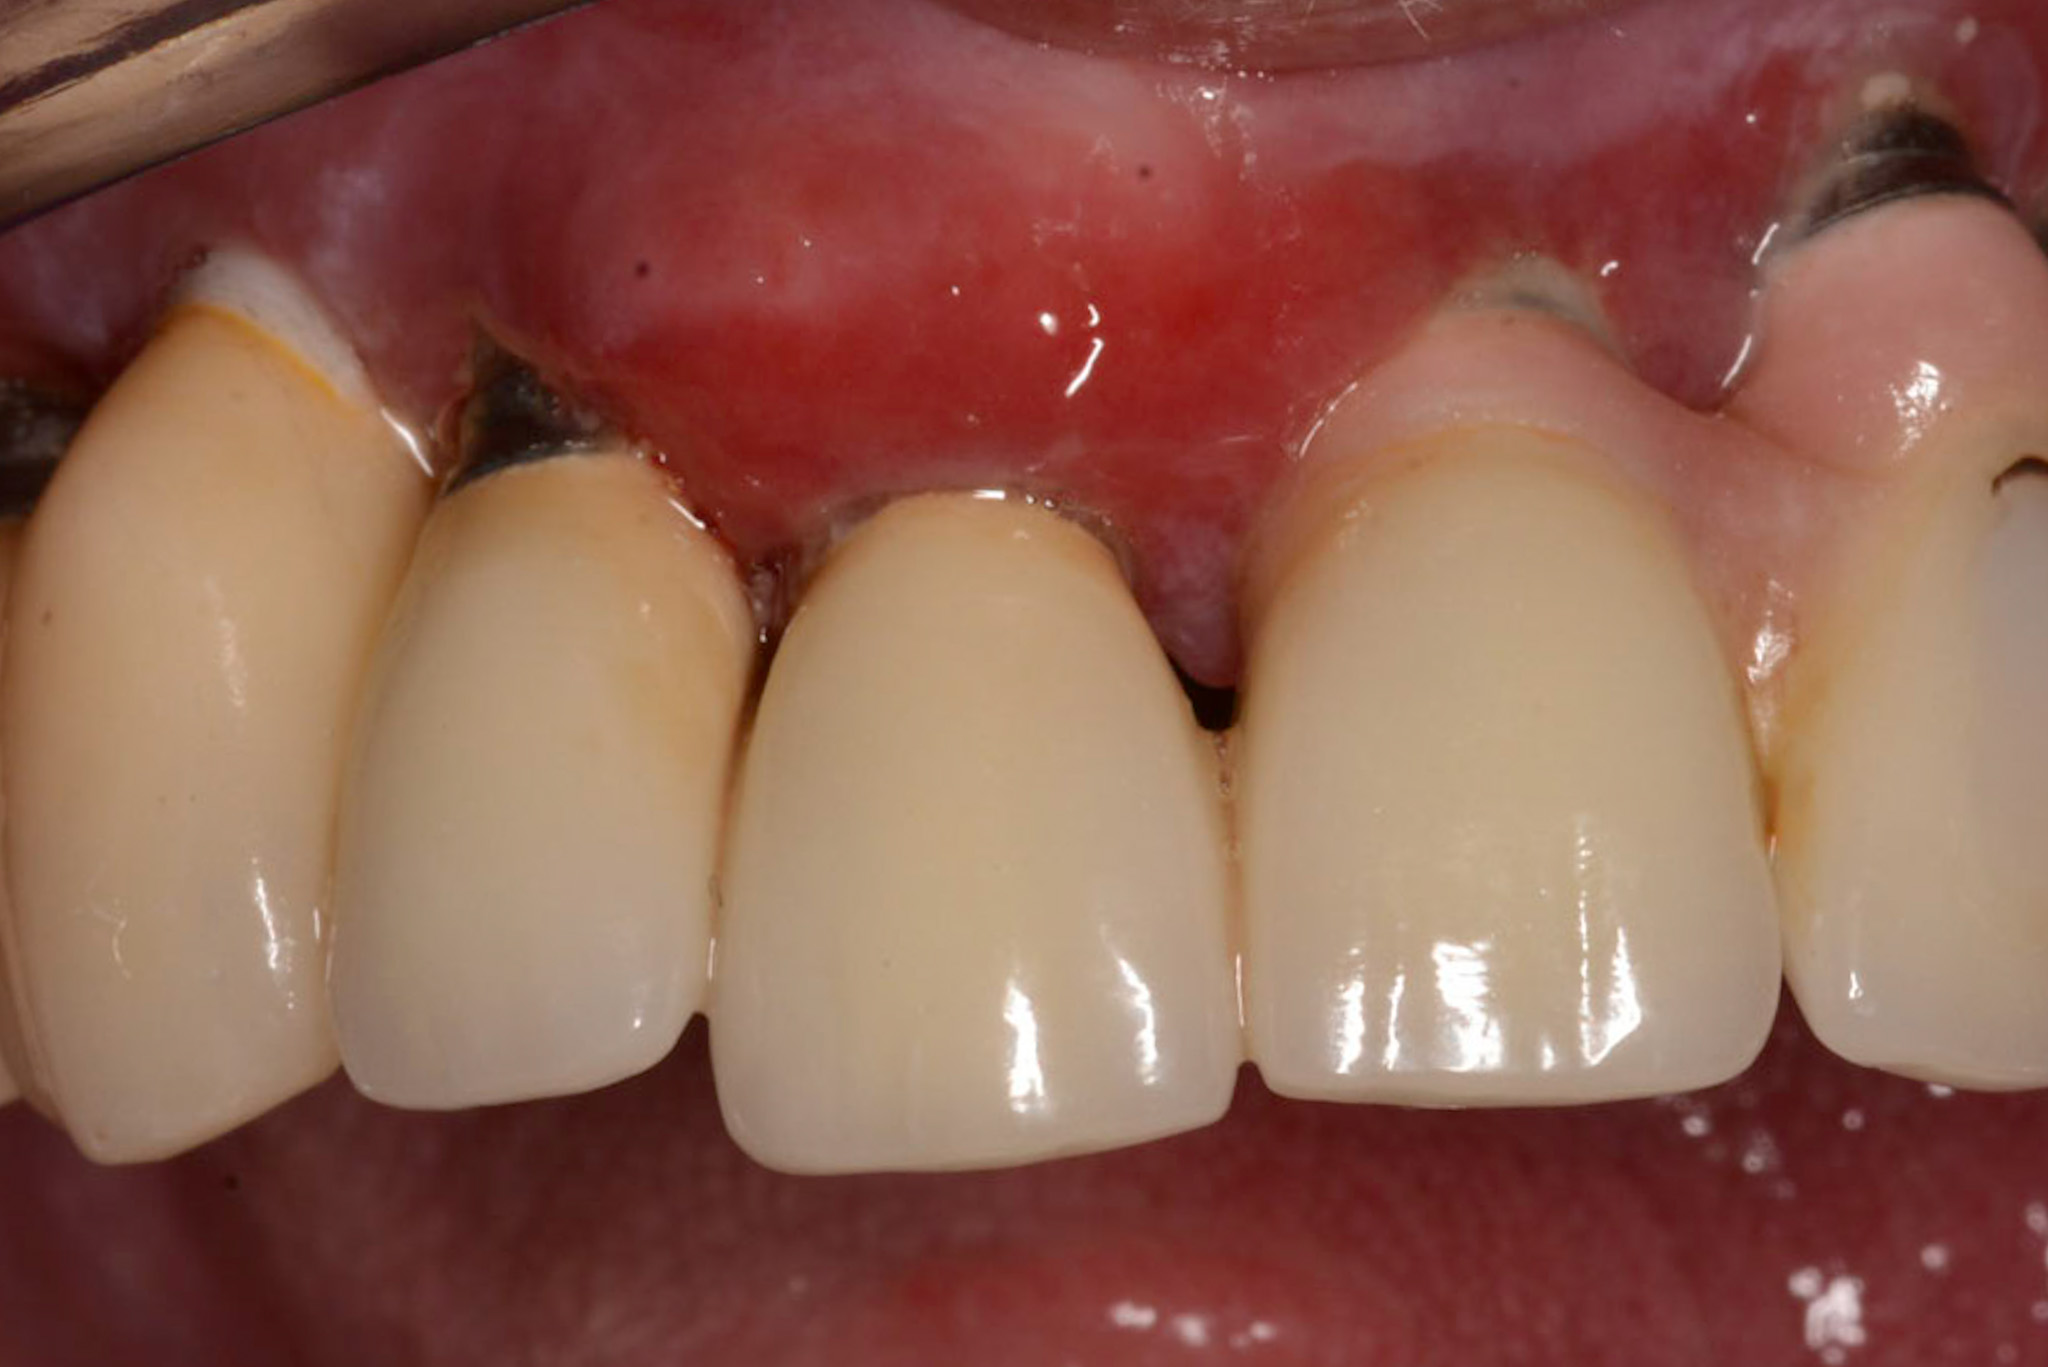

Klinisch ist eine atrophische Schleimhaut zu erkennen, diese ist sehr schmerzhaft für den Patienten. Weitere Symptome:

Ein erhöhtes Risiko für orale Mukositis besteht bei schlechter Mund- und Prothesenhygiene sowie bei Xerostomie. In der Anamnese können Risikofaktoren für eine bestehende medikamenteninduzierte Hyposalivation bereits erfasst und beim intraoralen Befund kann eine Mundtrockenheit erkannt werden (geringe Speichelfließrate, Spiegel bleibt an Mundschleimhaut kleben).